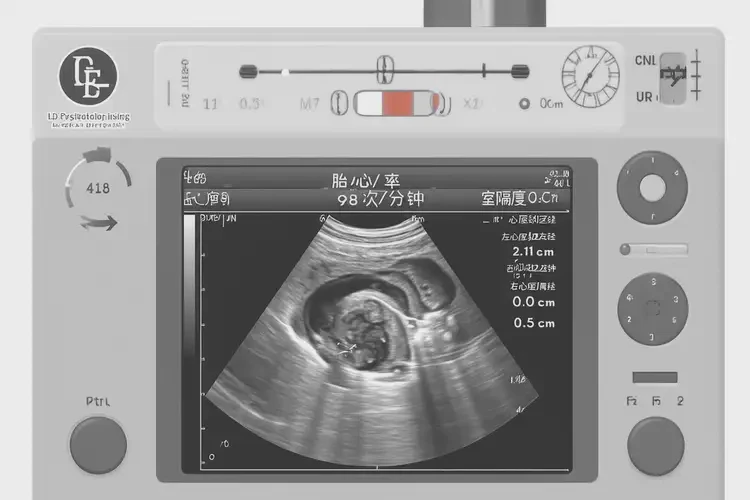

孕15周胎心98寶寶還能要嗎

胎心98次/分鐘在孕15周屬于正常范圍,寶寶可以繼續(xù)妊娠。

胎心率是指胎兒心臟每分鐘跳動的次數,是評估胎兒健康狀況的重要指標之一。在孕15周時,胎兒的胎心率通常在140-170次/分鐘之間。雖然98次/分鐘略低于正常范圍的下限,但并不意味著寶寶不能要。以下是詳細的解釋和建議:

孕15周胎心98寶寶還能要嗎(圖1)